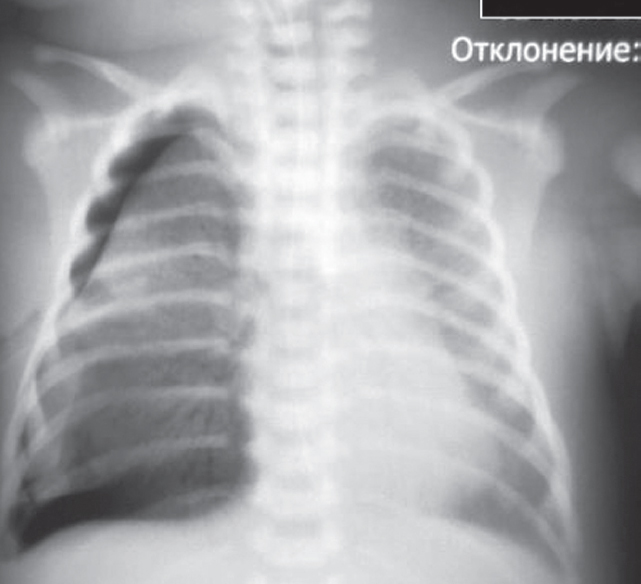

На контрольной рентгенограмме, выполненной на вторые сутки жизни (после введения сурфактанта), сохраняются признаки тяжелого РДС, осложнившегося правосторонним напряженным пневмотораксом (рис. 2), в связи с чем по экстренным показаниям было выполнено дренирование плевральной полости.

Рис. 2. Рентгенограмма органов грудной клетки новорожденного после введения сурфактанта

Fig. 2. Chest X-ray of newborn after surfactant administration